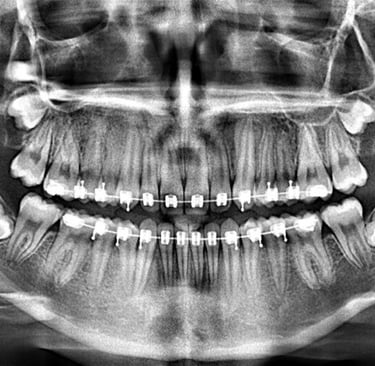

PANORÁMICA DIGITAL